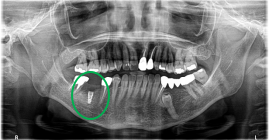

Before

※赤丸を抜歯しました。

After